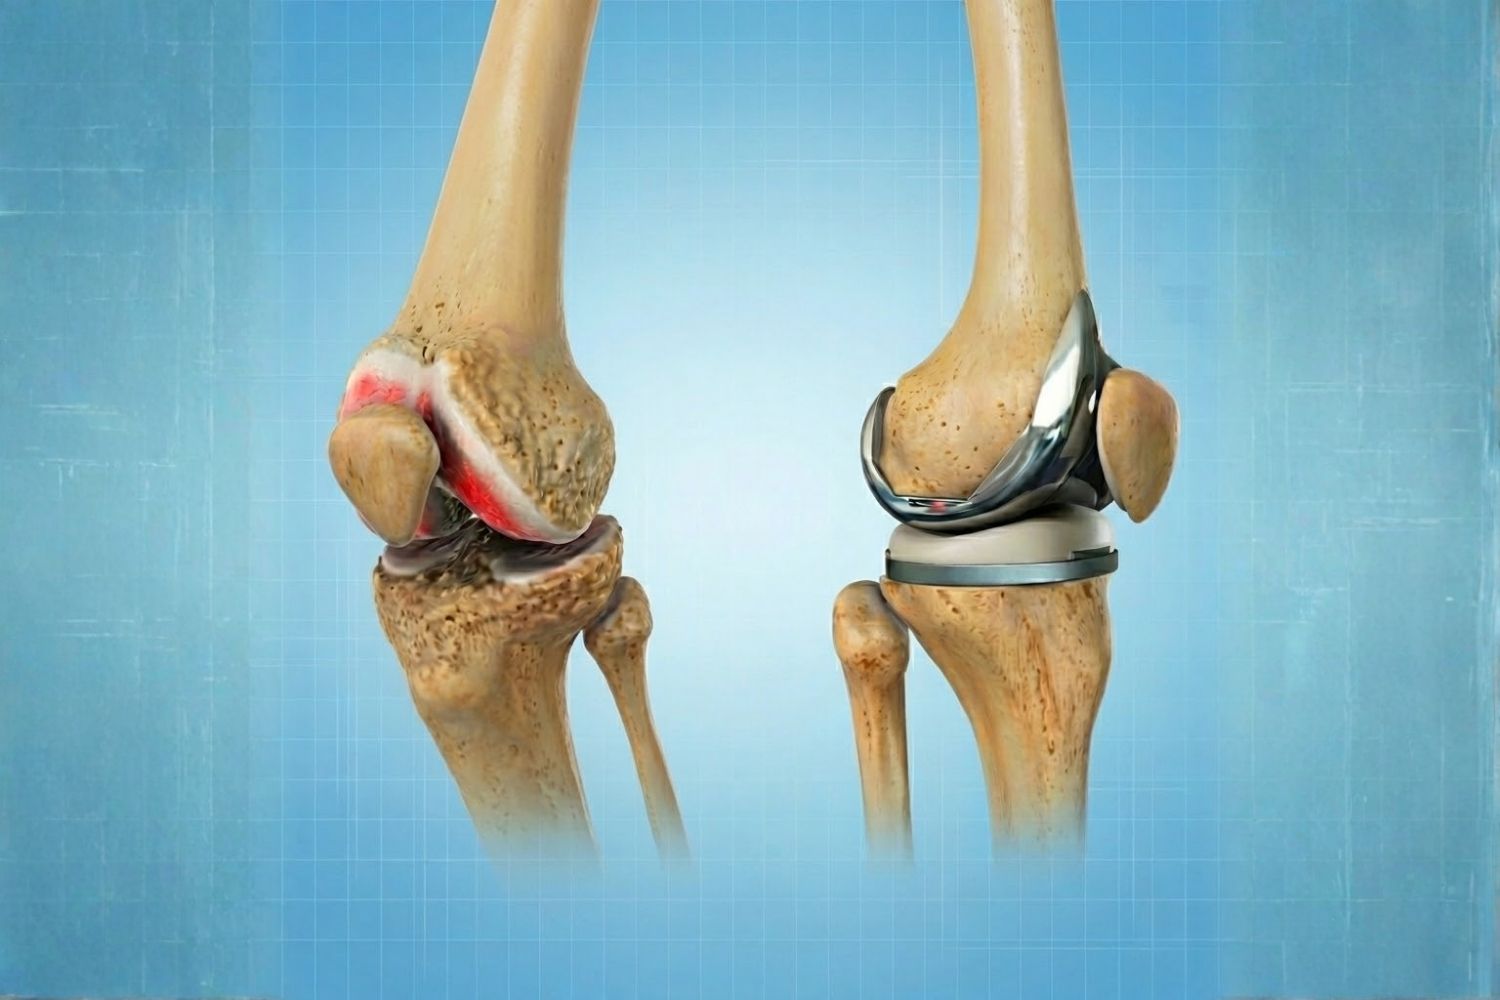

Prótesis articulares

Prótesis articulares (cadera, rodilla)

Reemplazo de la articulación desgastada o dañada por componentes artificiales de alta duración.

Reemplazo Articular de Rodilla en Lima

Prótesis de Rodilla

Olvídate del dolor con una prótesis de rodilla. Nuestro equipo te brindará una solución personalizada para que puedas volver a disfrutar de tus actividades favoritas.

Recupera la movilidad y olvida el dolor de la artrosis avanzada con el reemplazo articular total.